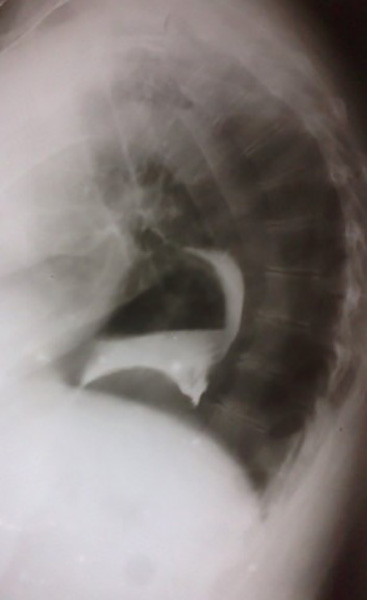

How do ulcers appear on contrast studies?

Appear as outpouchings due to surrounding mucosal edema (not true outpouchings).

How are ulcers classified by location?

Gastric (stomach) vs duodenal (duodenal bulb or pylorus).